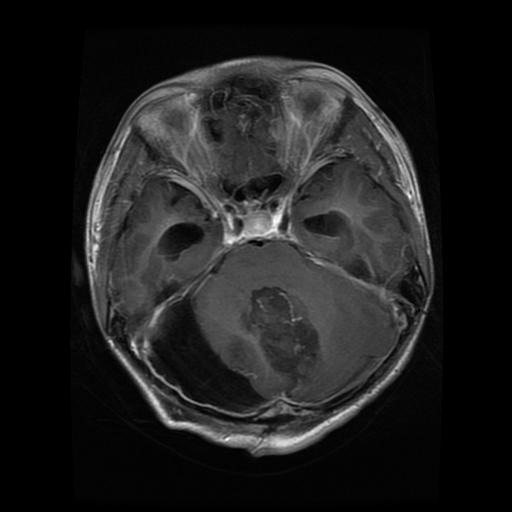

Refer to caption

Figure 1: MRI Scans Showing Various Conditions: Glioma, Meningioma,a Non-Tumor Case and Pituitary Tumor

A few images from each class were visually inspected to understand dataset balance and quality, with examples shown in Figure 1. The varying nature of gliomas, meningiomas, pituitary tumors, and non-tumor cases hence brought a firm rationale before the model building and evaluating stages.